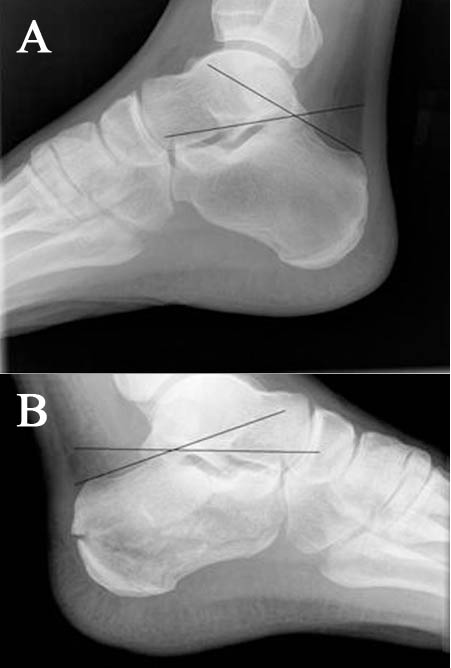

- (A) Normal Boehler's angle and (B) Abnormal Boehler's angle

- Decreased Boehler's angle (<25') may be only sign of fx (compare w/ opposite side)